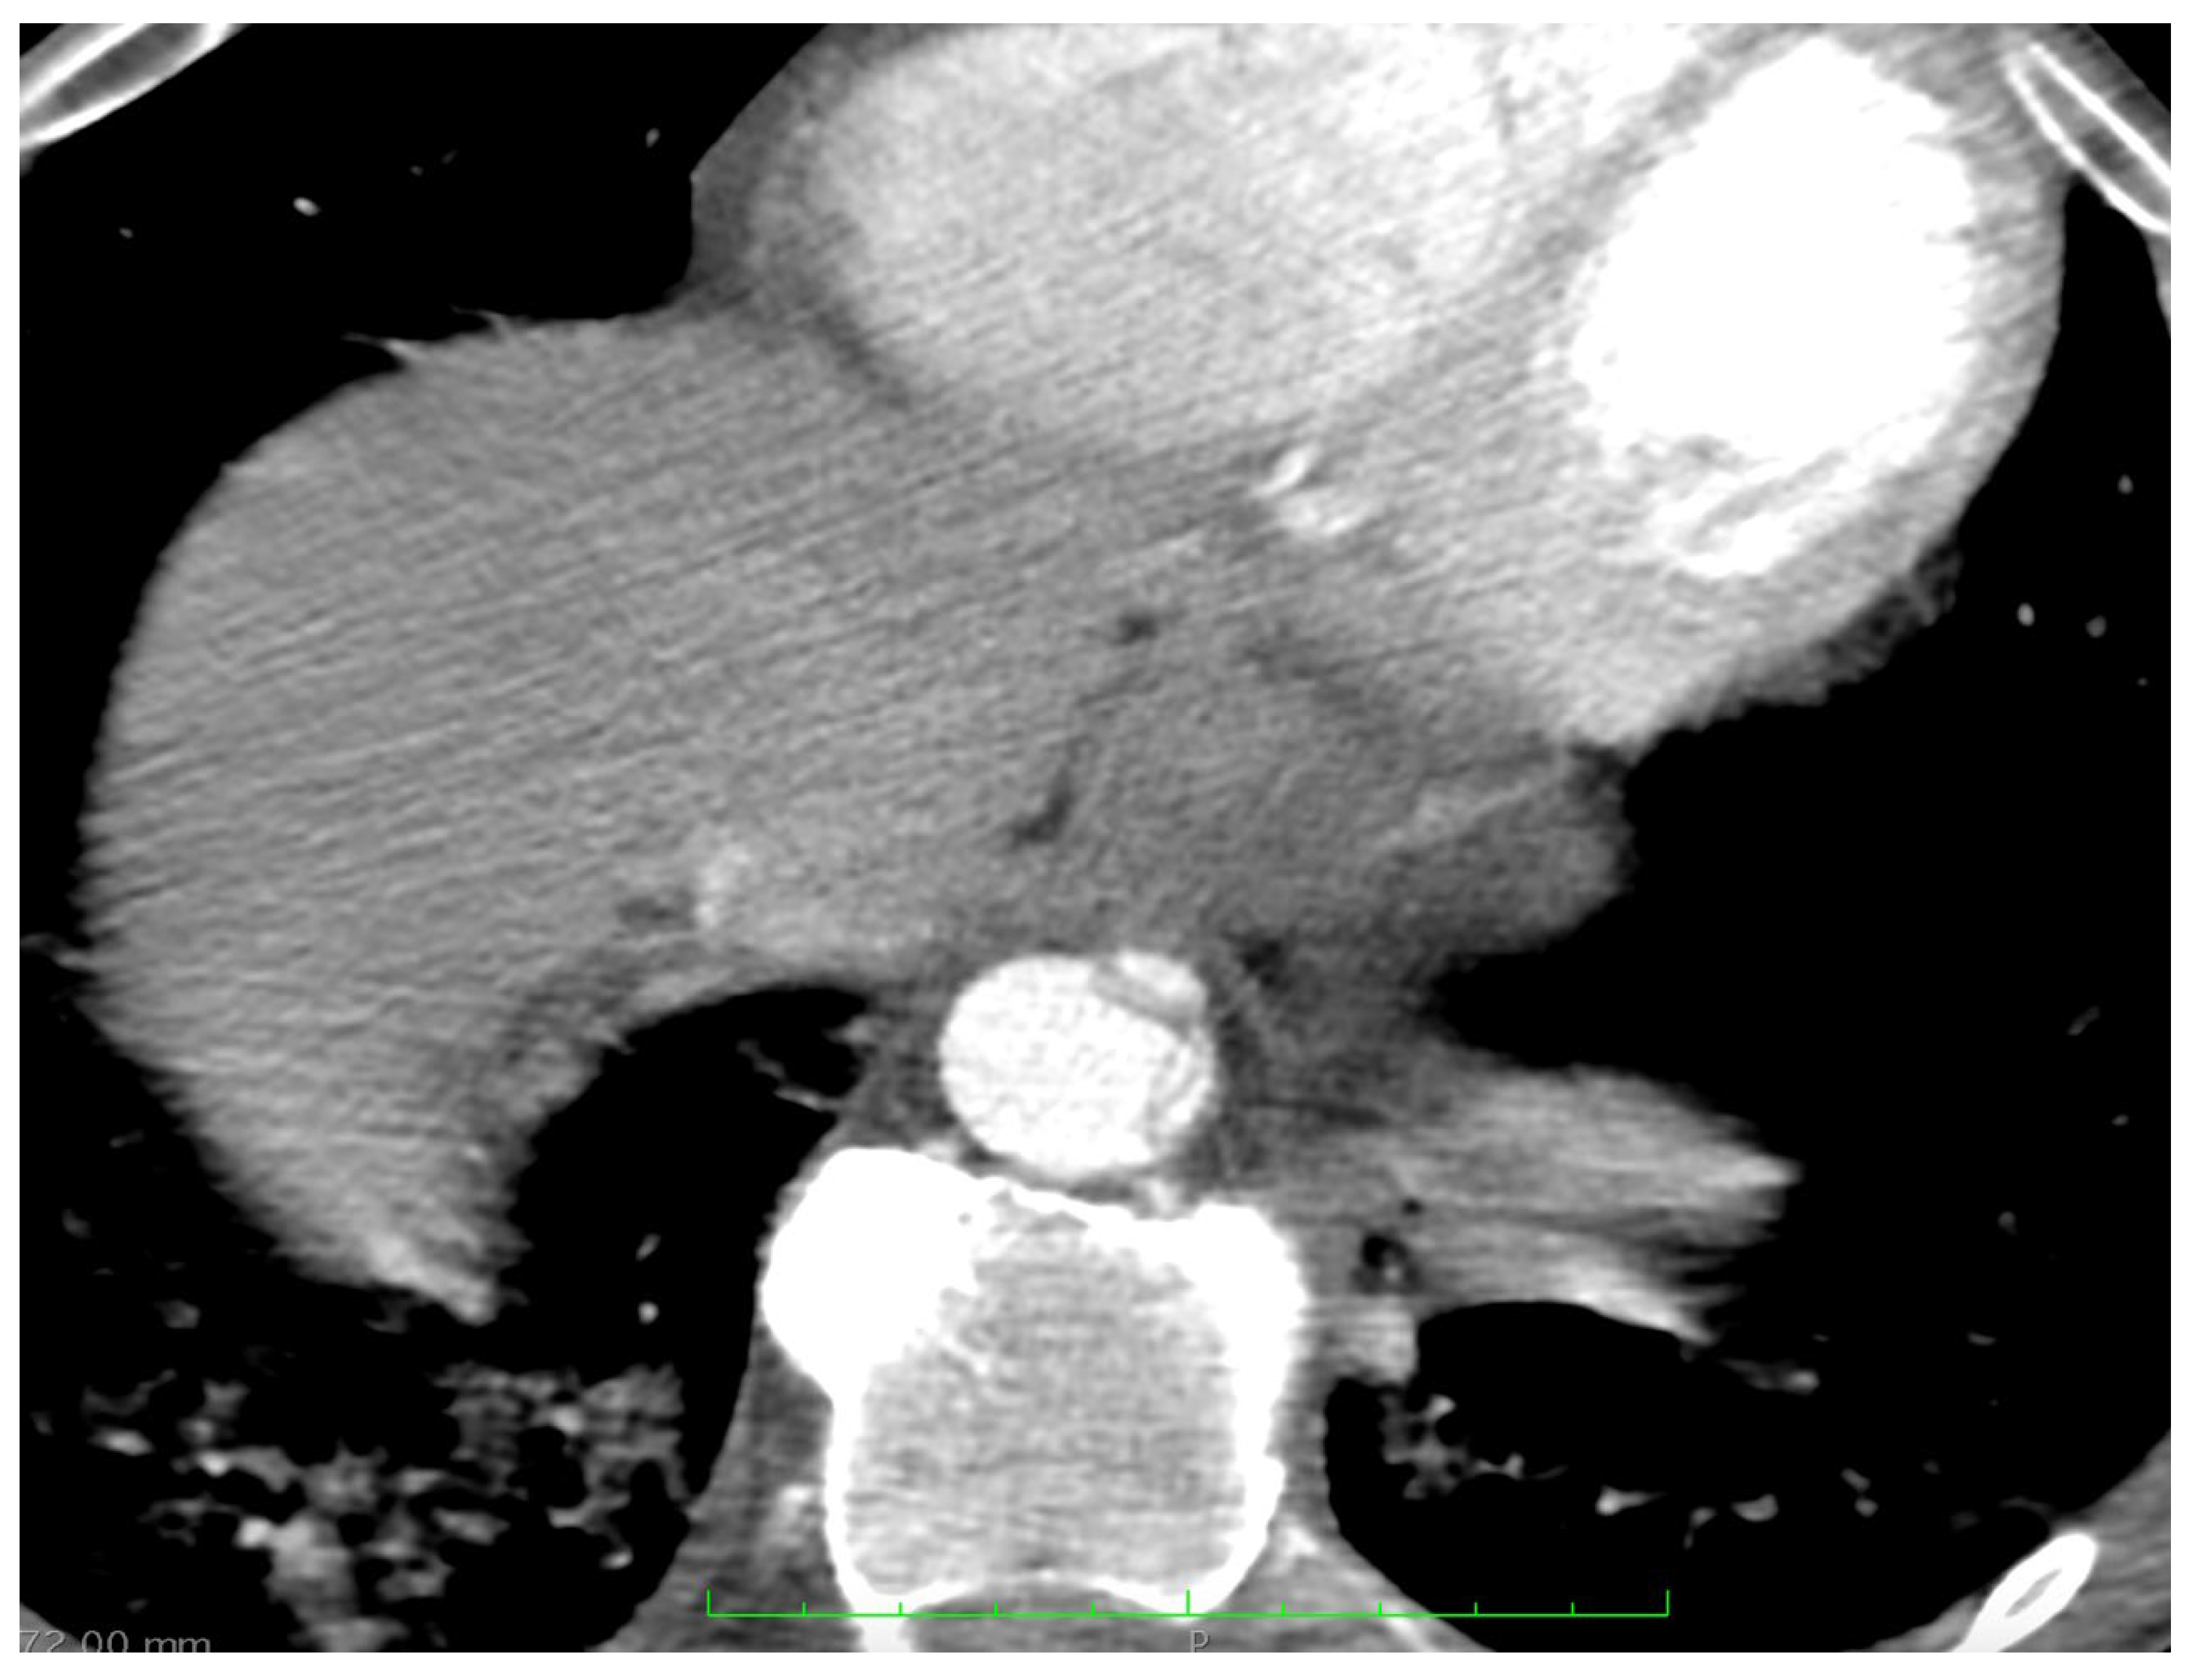

2. Case Report